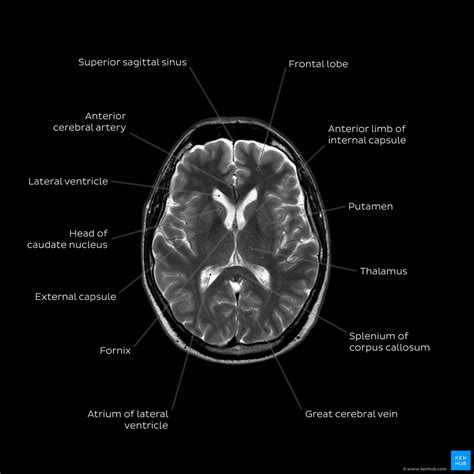

First look mri can provide a video report created by our experienced radiologists using lay terms. A neurological exam tests different parts of your brain to see how they're working. Through the help of the tissue’s proton or hydrogen level! It is the process by which magnetic fields & radio waves lead to the generation of a detailed image of your brain structures; T2 is generally the more commonly used, but t1 can be used as. Brian gay provides an easy to understand explanation of an mri brain scan and how to read it. Web mri brain is a specialist investigation that is used for the assessment of a number of neurological conditions. Web an mri of the brain is the most commonly performed medical imaging test in 2022. Brain mri examination should follow a systematic approach starting from the midline and going laterally. Web diagnosis meningioma brain tumor mri if your health care provider thinks you might have a brain tumor, you'll need a number of tests and procedures to be sure.

It is the process by which magnetic fields & radio waves lead to the generation of a detailed image of your brain structures; Brain mri examination should follow a systematic approach starting from the midline and going laterally. Web how to read brain mri. Web an mri of the brain is the most commonly performed medical imaging test in 2022. Web diagnosis meningioma brain tumor mri if your health care provider thinks you might have a brain tumor, you'll need a number of tests and procedures to be sure. Clinicians use various mri techniques to observe & assess brain anatomy. A neurological exam tests different parts of your brain to see how they're working. It is the process by which magnetic fields & radio waves lead to the generation of a detailed image of your brain structures; Conversely, the cerebrospinal fluid (csf) is bright in t2 due to its’ water content. Thus, the brain mri analysis shall start from the ventricles, going to the surrounding subcortical structures, brain lobes, cerebral cortex, to the meninges and skull. First look mri can provide a video report created by our experienced radiologists using lay terms.